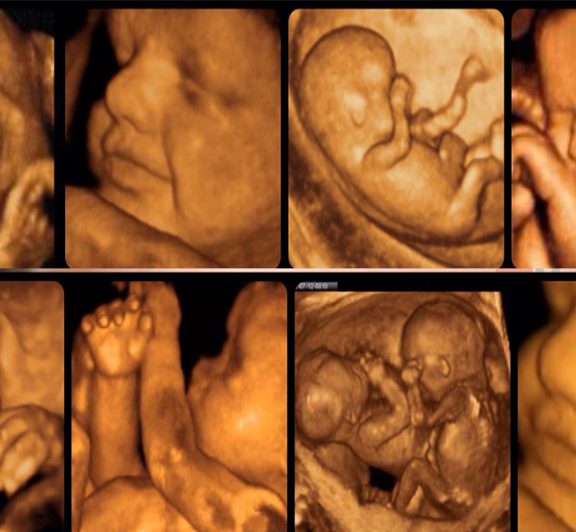

Dört Boyutlu Ultrason

More Details